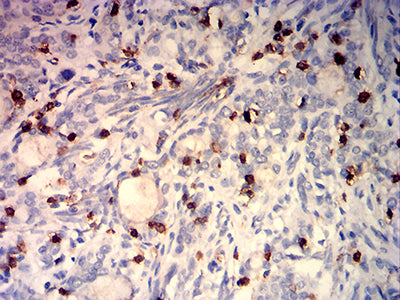

分类: 科研抗体货号: 32270别名: CMH2; RCM3; TnTC; cTnT; CMD1D; CMPD2; LVNC6应用: IHC,FCM反应种属: Human